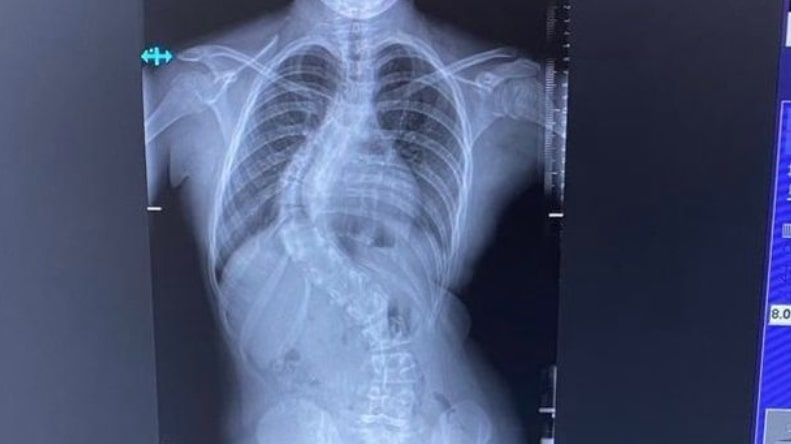

經X光檢查竟發現其脊椎呈80度彎曲。醫生推斷可能是因女孩急速長高、一年就長高7厘米所導致的。

醫生指,針對女孩的情況,已無法透過配戴支架改善,故需做手術。「如果不及早手術,脊椎彎曲惡化可能會擠壓到肺部和心臟。」